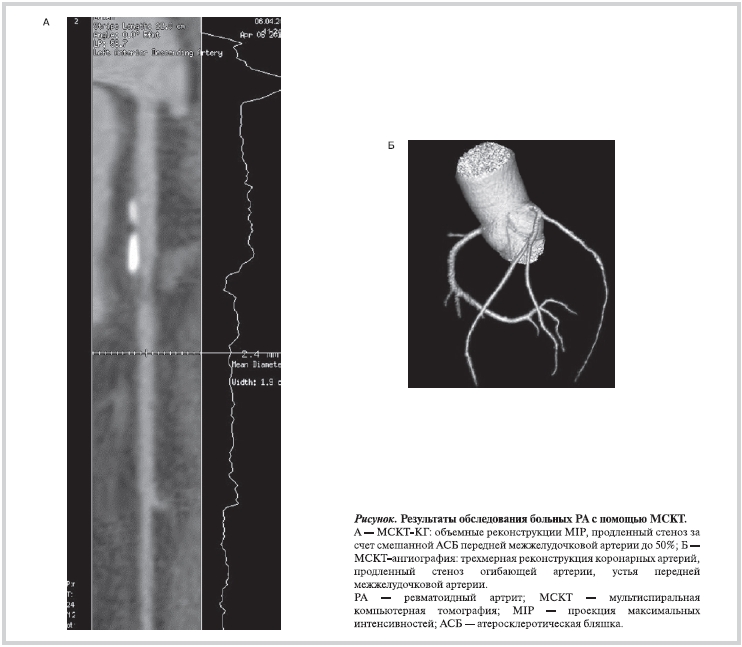

В 3 (60%) случаях из 5 у больных РА диагностировано более одной атеросклеротической бляшки (АСБ) с локализацией в правой, левой коронарных и передней межжелудочковой артериях (см. рисунок). У лиц контрольной группы имелись лишь одиночные АСБ в передней межжелудочковой артерии.

Женщины с РА и гемодинамически значимым стенозом (80 и 50%), обусловленным атеросклеротическим поражением КА, были в возрасте 38 и 53 лет, имели 3-ю степень активности ревматоидного воспаления (индекс DAS 28 составил 6,09 и 6,25 соответственно), серопозитивный вариант РА (титр РФ 101,7 и 187,7 МЕ/мл соответственно), развернутую и позднюю клиническую стадию с функциональной недостаточностью суставов 2-й и 3-й степени. Уровень С-реактивного белка составил 17,2 и 11,4 мг/л, скорость оседания эритроцитов — 29 и 36 мм/ч соответственно. Дислипидемия диагностирована у одной пациентки 53 лет с выявленным 50% стенозом КА.